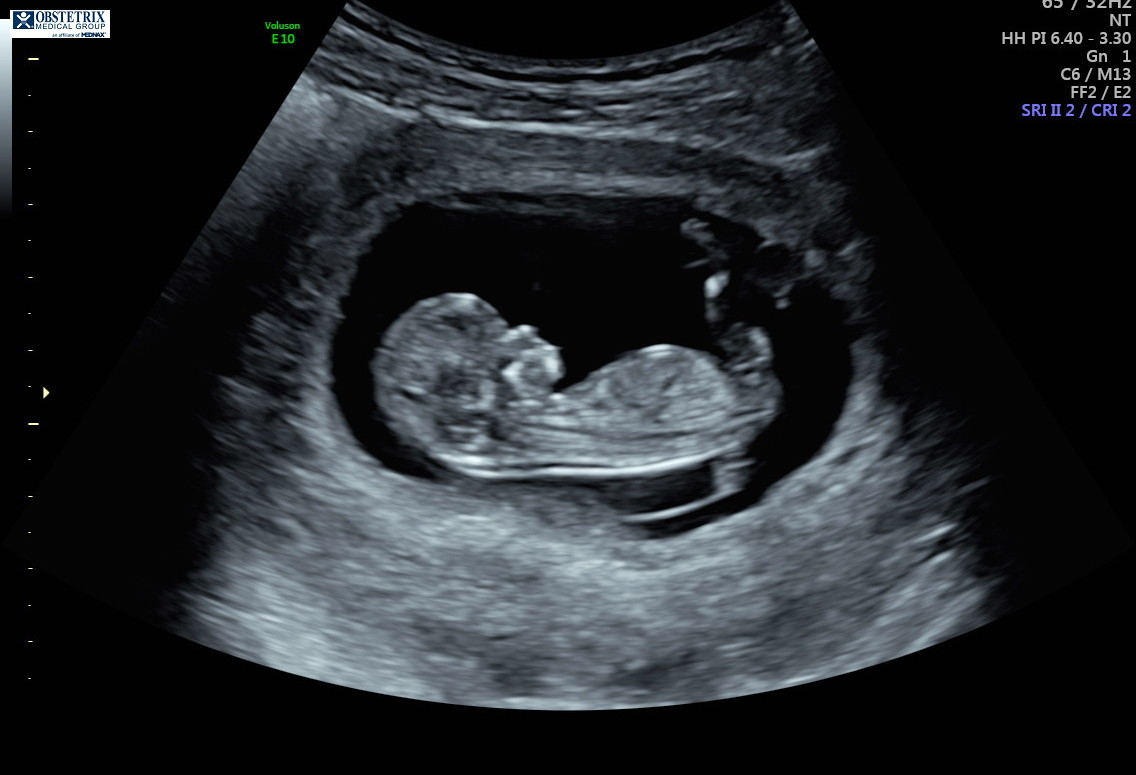

Hello! The photo is from my 12 week ultrasound. I’ve been reading up on the nub theory because I’m dying to know the sex, but I can’t decide if it looks more girly or boyish. Any thoughts are appreciated!!!!

“Experts” on the nub theory my friend. Yes, I have talk to doctors about it. Yes, some do believe in the nub theory while others are afraid to guess because they are afraid to guess wrong and upset anyone which makes sense. No, it is not always accurate and if you try the nub theory generally you know not to take to it too seriously until the anatomy scan. Also this theory will not hurt the baby so no harm done. But if you can’t handle the possibilty of a wrong guess then don’t even try asking for a guess. It’s for fun. Have you read up on it even? The nub sits flat with the back if it’s a girl and it’s angled up from the back if it’s a boy. I have 2 girls and 1 boy so I am pretty sure it’s not “luck” just really good scans! The “experts” on the nub theory have guessed correctly with my ultrasound pictures. I have also done the NT scans which is around the right time to make a guess with the nub about 11-13 weeks I believe. The doctor agreed that it can be accurate if done properly. You must have a perfect nub picture ( a full body side view of fetus without their back curled during 11-13 weeks) to get a pretty accurate guess. Notice my use of guess? Yes, still 50/50 and yes, doctors still get the anatomy scan wrong too so you can’t be 100% sure until birth if you are want total accUracy. Do some reading up. I found it very interesting when I had my first child. But it is called a theory for reason.

“Experts” on the nub theory my friend. Yes, I have talk to doctors about it. Yes, some do believe in the nub theory while others are afraid to guess because they are afraid to guess wrong and upset anyone which makes sense. No, it is not always accurate and if you try the nub theory generally you know not to take to it too seriously until the anatomy scan. Also this theory will not hurt the baby so no harm done. But if you can’t handle the possibilty of a wrong guess then don’t even try asking for a guess. It’s for fun. Have you read up on it even? The nub sits flat with the back if it’s a girl and it’s angled up from the back if it’s a boy. I have 2 girls and 1 boy so I am pretty sure it’s not “luck” just really good scans! The “experts” on the nub theory have guessed correctly with my ultrasound pictures. I have also done the NT scans which is around the right time to make a guess with the nub about 11-13 weeks I believe. The doctor agreed that it can be accurate if done properly. You must have a perfect nub picture

( a full body side view of fetus without their back curled during 11-13 weeks) to get a pretty accurate guess. Notice my use of guess? Yes, still 50/50 and yes, doctors still get the anatomy scan wrong too so you can’t be 100% sure until birth if you are want total accUracy. Do some reading up. I found it very interesting when I had my first child. But it is called a theory for reason.